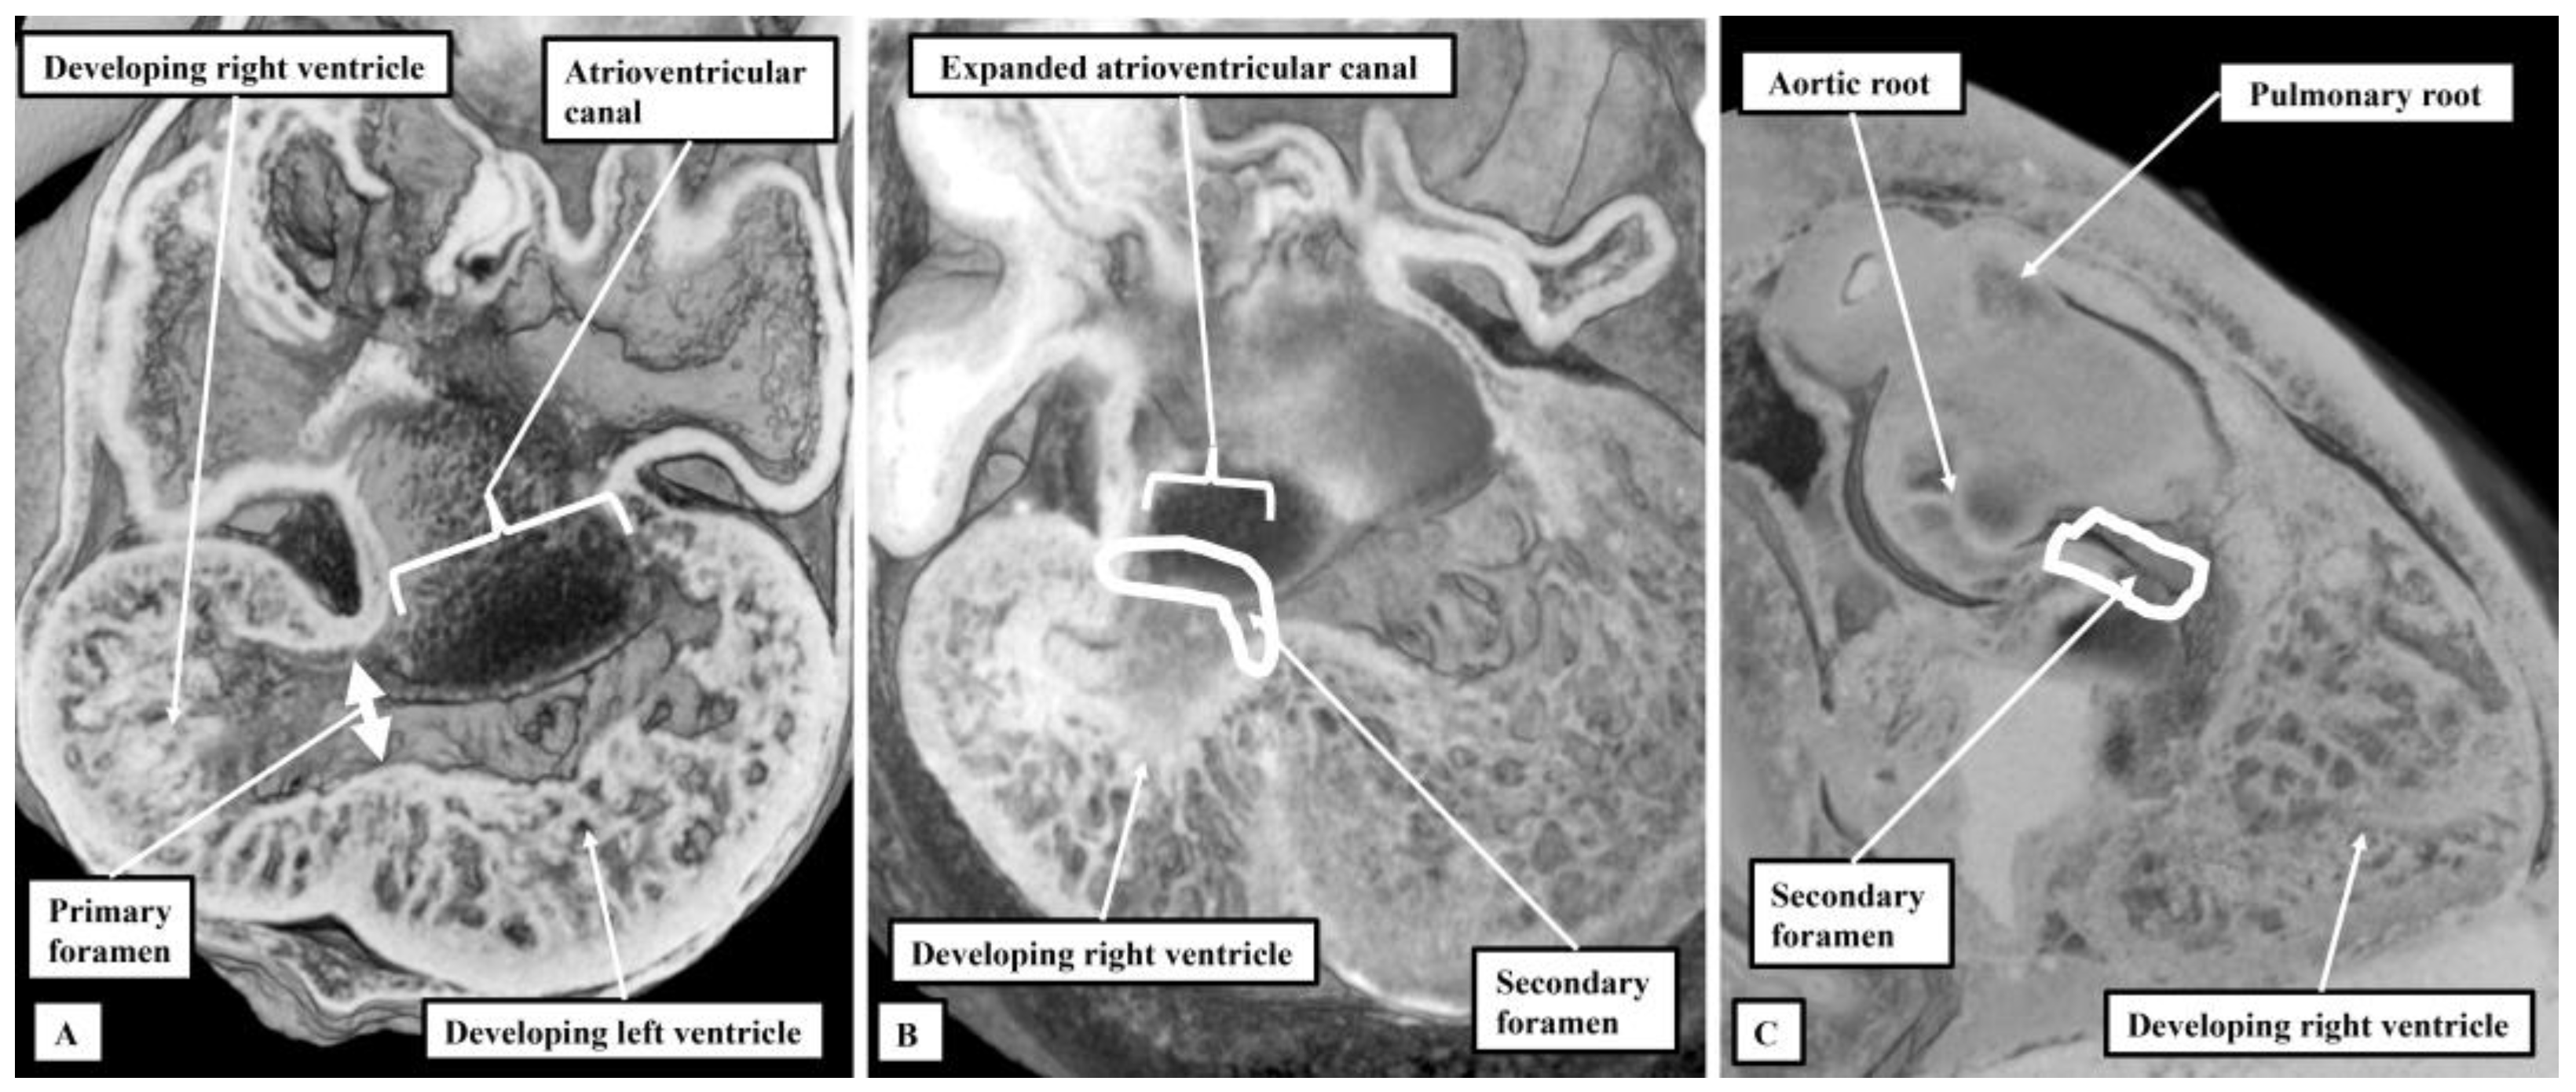

Hypoplastic left heart syndrome: MedlinePlus Medical。What Is the Hypoplastic Left Heart Syndrome?。Hypoplastic Left Heart Syndrome: A New Paradigm for an Old。心臓の血流と酸素飽和度に関する専門的な情報が掲載された書籍。。What Is the Hypoplastic Left Heart Syndrome?。- タイトル: Hypoplastic Left Heart Syndrome- 編集者: Hani A. Hennein, MD, Edward L. Bove, MD- 内容: 心臓の血流と酸素飽和度に関する詳細な情報- ISBN: 0-87993-704-1裏表紙に記名あり黒マッキーで塗り潰しますご覧いただきありがとうございます。